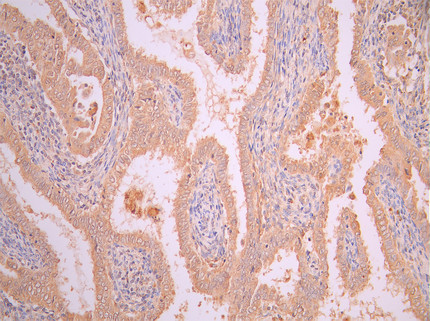

FAP的表达模式使其成为潜在的生物标志物和治疗靶点。研究表明,FAP在超过90%的癌症类型(如乳腺癌、胰腺癌、食管癌和肺癌)中的癌症相关成纤维细胞(CAFs)上高度表达,而在健康成人组织中几乎不表达 [2][3][5][6]。这种病理特异性表达赋予了FAP作为癌症诊断和治疗靶点的巨大潜力 [6]。

FAP作为肿瘤微环境中的关键靶点,其在肿瘤的侵袭、转移、免疫逃逸以及耐药性中发挥重要作用。华美生物提供FAP重组蛋白、抗体及ELISA试剂盒产品,助力您开发特异性靶向FAP的药物,探索其在肿瘤治疗中的应用潜力。

● FAP抗体

FAP Recombinant Monoclonal Antibody; CSB-RA008424MA1HU

FAP Recombinant Monoclonal Antibody; CSB-RA008424MA2HU